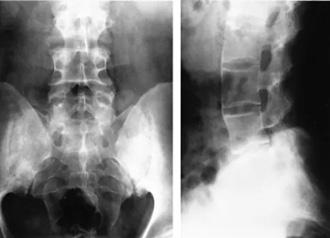

Figura 14. Sacroileitis

Radiografías simples de la columna y la pelvis como técnicas de imagen iniciales